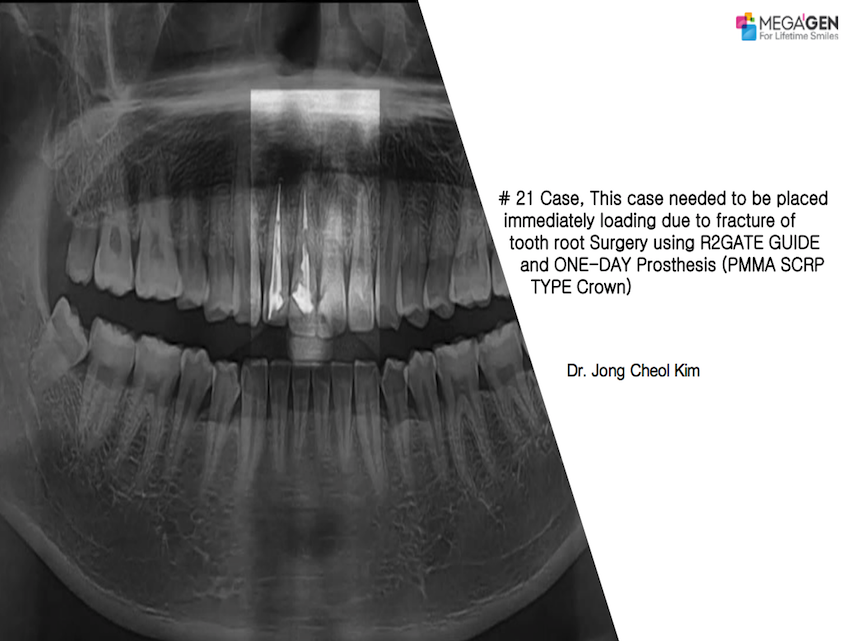

#26,AnyRidge,Bone regeneration,Digital Guided Surgery,Dr. Antonio Cabral de Campos Felino,Dr. Isabel Maria Lopes Guerra,Dr. Mario Ramalho de Vasconcelos,Dr. Raquel Zita Gomes,Dr. Rute Alexandra Borges de Almeida,Immediate Placement,Maxillary Posterior,MEGA ISQ,Publication,R2GATE,R2GATE Guide,Single replacement,Xpeed